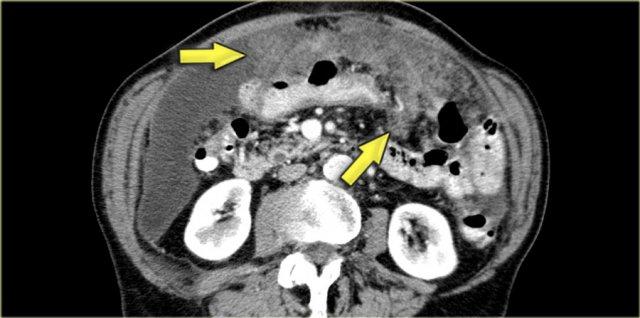

Hình bên trái là bệnh nhân với u carcinoid điển hình có vôi hóa trung tâm (mũi tên xanh dương).

Lưu ý hiện tượng co kéo ruột và dày thành ruột.

Có di căn gan (mũi tên vàng).

Hình bên trái là một bệnh nhân khác mắc u carcinoid.

Trong trường hợp này, chúng ta cũng có thể phát hiện di căn gan trên hình chụp (mũi tên xanh dương).

Lưu ý không có hoạt động của khối u nguyên phát ở ruột non.

Điều này thường gặp vì khối u nguyên phát có thể khá nhỏ.